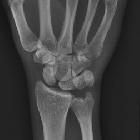

In addition to stating that a lunate dislocation is present, a number of features should be sought and commented upon:

- dislocation

- ensure that radiolunate alignment is disrupted, and that you are not looking at a perilunate dislocation (stage II carpal dislocation)

- evaluate and comment on the degree or palmar rotation of the lunate (this can be up to 270 degrees)

- ensure that the capitate remains co-linear with the long axis of the radius

- any additional fractures